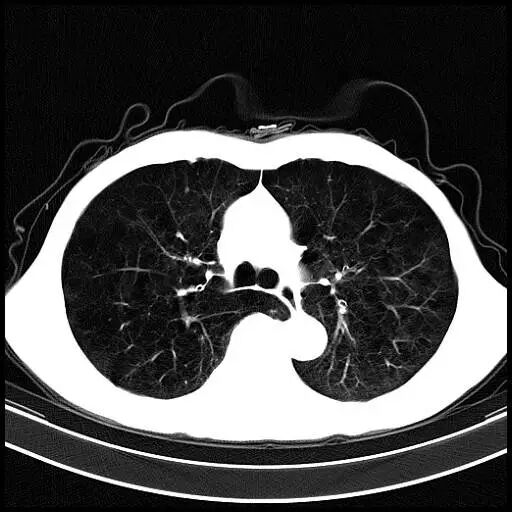

正常肺的CT表现

图片

图3

胸廓的横径和前后径的比例是3:2,双肺纹理走行自然,像树杈一样分支越来越细,直达肺的边缘,肺野内未见异常密度影。正常的肺泡直径平均只有0.2 mm左右,CT是看不见的。